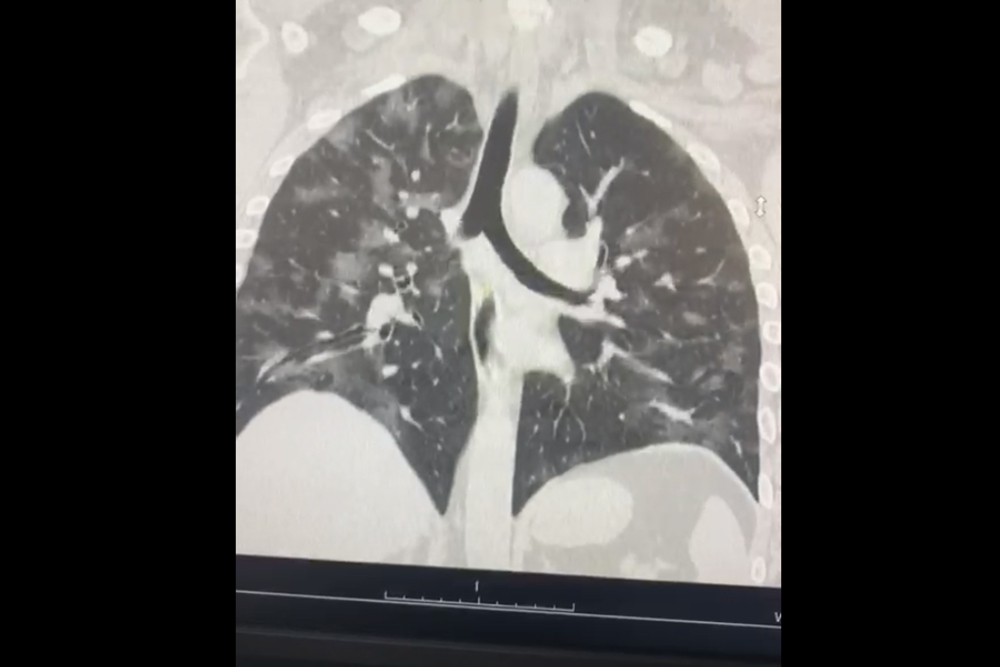

– Доля легких форм заболевания в первой группе, практикующей аэробный тренинг, при исключении случаев бессимптомного течения, составила 95 процентов, тогда как во второй группе – 66,5 процентов. У лиц, адаптированных к аэробной нагрузке, по характеристике клинических вариантов болезни существенно чаще всё ограничивалось ОРВИ, а пневмония с острой дыхательной недостаточностью диагностирована всего у одного больного (мужчина 57 лет), у которого заболевание квалифицировано как среднетяжелое, – прокомментировал Андрей Юрьевич.